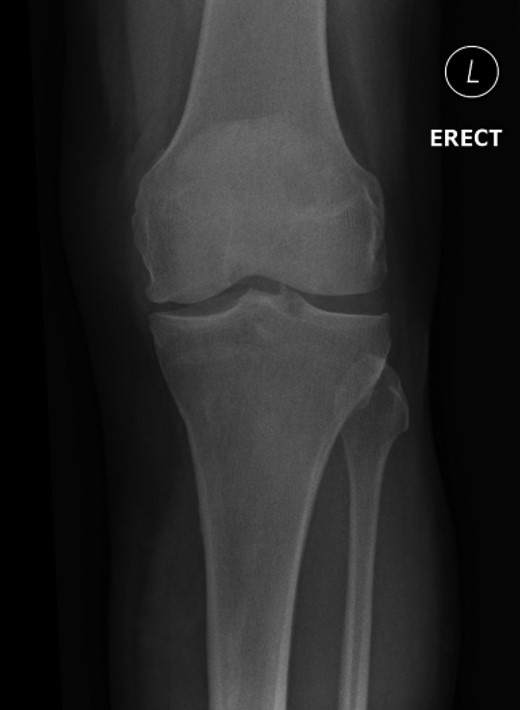

Nineteen months earlier the patient had consulted his general practitioner complaining of left knee pain. Radiographs performed at that time were reported to show joint space narrowing within the patello-femoral compartment as well as early joint space narrowing within the medial compartment. A subchondral lucency was also noted within the patella which was described as a subarticular cyst secondary to the previously mentioned patello-femoral degeneration (Figs 1–3).

The absence of associated features of systemic disease, as well as radiographic appearances in keeping with early patello-femoral osteoarthritis (OA), account for the delay in diagnosis. The initial images suggest mild degeneration but, whilst subarticular cysts are a radiographic feature of OA, the lesion shown in this case is larger than would be expected with the level of disease shown elsewhere in the joint.